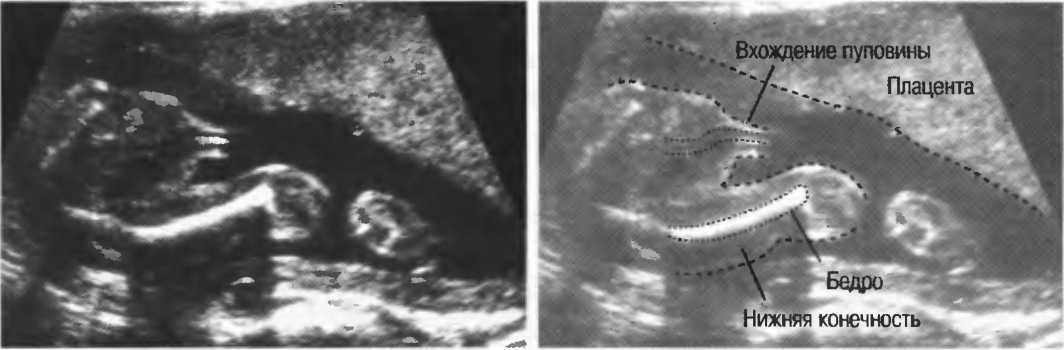

Рис.5. Два поперечных среза плода, демонстрирующих тень от позвоночника плода. Аналогичная тень от ребер может частично закрывать почки или печень. Изменяя угол наклона датчика, можно изменить положение тени таким образом, чтобы подлежащие ткани были видны отчетливо.